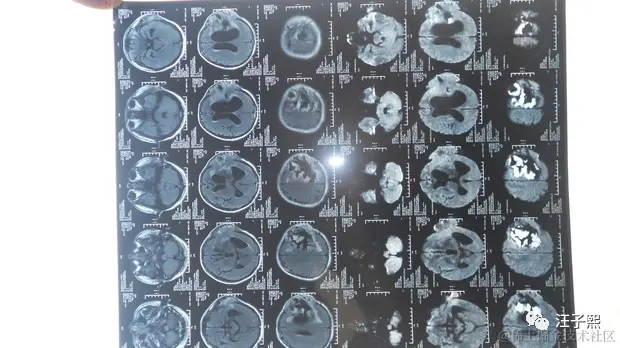

Jerry之前的文章 记一次SAP开发工程师给微软Azure报incident的体验,也提到自己处理incident和给别的程序员报incident的经历,没想到,这次有医生给我身上这台生物系统报了incident,而且priority还是very high的。一个专业的程序员,在接到incident之后,都是从“问题重现-问题定位-设计解决方案-处理问题-测试”这几个步骤进行的。我最近,凭着Google和金山词霸,也在看相关的英文论文,从病的诱因,诊断,治疗和预后这几个方面来学习,恶补了一大堆理论知识,虽然对我实际可能没什么用,甚至会让我的情绪变得消极,然而我的这些行为都是一个程序员的职业习惯使然——不管遇到什么问题都想刨根究底。